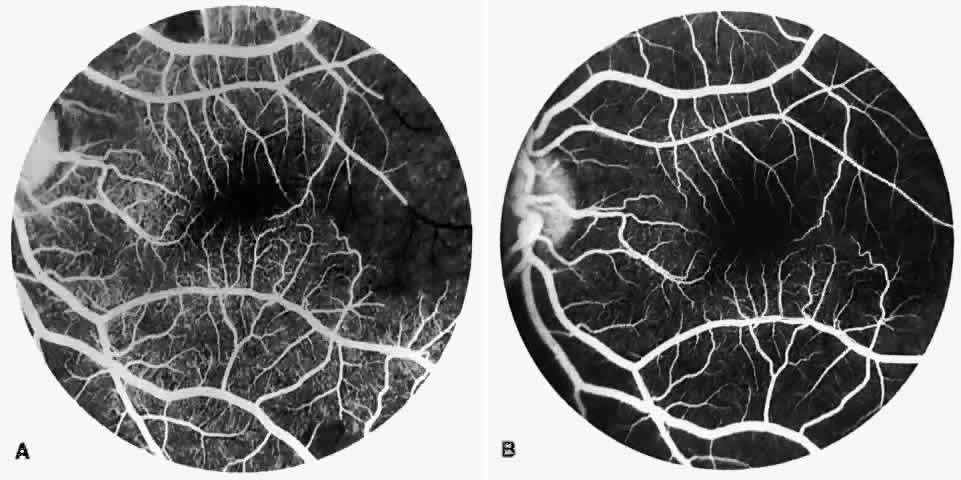

Other macular and perimacular changes include microaneurysm-like dots, dark and enlarged segments of arterioles, hairpin-shaped venular loops, pathologic avascular zones, and widening and irregularities of the foveal avascular zone (Figs. 11 and 12). In the Jamaican cohort study evaluating children with homozygous sickle cell anemia and SC disease between the ages of 5.0 and 7.5 years of age, no pathologic avascular zones could be identified despite a high incidence of peripheral vascular closure.31 In evaluating patients with homozygous sickle cell anemia, no relationship between ISC counts and macular abnormalities or visual acuity could be found.101 Using fluorescein angiography, investigators have found the foveal avascular zone to be significantly larger in eyes with clinical evidence of sickle cell maculopathy as compared with normal eyes and eyes without clinical evidence of sickle cell maculopathy.102–104

Fig. 11. A. A 40-year-old woman with homozygous sickle cell anemia. A fluorescein angiogram demonstrates multiple microaneurysm-like dots with fluorescein leakage, hairpin loop (arrowhead), pathologic avascular zones (arrows), and a widened, irregular foveal avascular zone (FAZ). B. Fluorescein angiogram of a 30-year-old woman with homozygous sickle cell anemia demonstrates multiple microaneurysm-like dots and a widened, irregular FAZ.

Fig. 12. A. Fluorescein angiogram of the left eye of a 40-year-old man with homozygous sickle cell anemia, demonstrating an irregular foveal avascular zone (FAZ), hairpin loops, and loss of the temporal capillary network. B. Fluorescein angiogram of the right macula of a 38-year-old woman with homozygous sickle cell anemia, showing an abnormal FAZ, hairpin loop (arrowhead), and pathologic avascular zones (arrows).